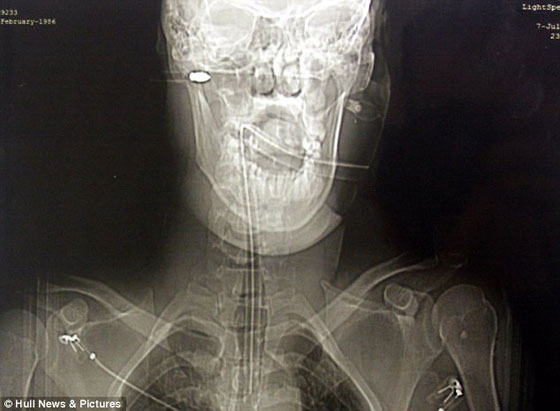

وقالت صحيفة "الديلي ميل" البريطانية الشاب اللتواني نقل سريعاً إلى المستشفى، وأجرى له الجراحون جراحة سريعة نزعوا السهم منه، ولكن ظل رأسه، الذي يبلغ طوله ثماني بوصات، داخل جمجمته ولم يتم استخراجها خوفاً على حياته. وقالت إدارة المستشفى إن الشاب كان على وشك أن يفقد حياته، لو كان الرأس تحرك بضعة مليمترات فقط، حيث كان على بعد مليمتر واحد من الشريان السباتي، ما كان سيجعله يفقد حياته أو تصيبه أعراض خطيرة مثل الشلل النصفي.